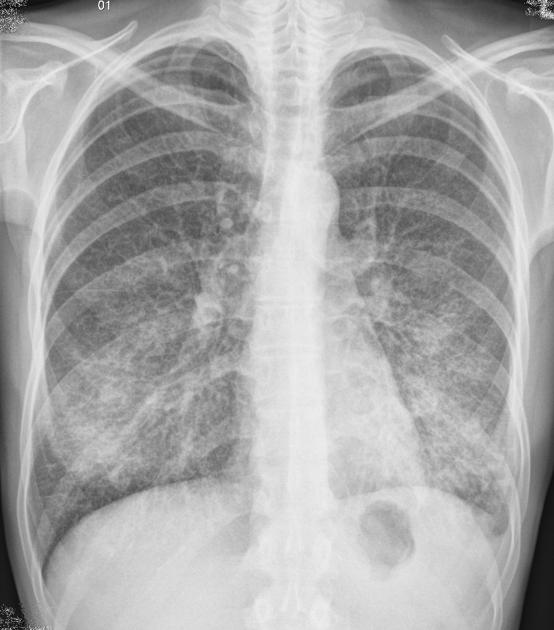

Пневмониялы өкпе

COVID-19 пневмониясы

Бұл зерттеу жұмысының барысында біз өкпе ауруларын, әсіресе пневмонияны анықтауда жасанды интеллектіні (ЖИ) қолданудың маңызын қарастырдық. Өкпенің сау және ауру түрлерінің рентген суреттерін салыстыру арқылы пневмонияның негізгі белгілерін айқындауға болады. Дәстүрлі әдістермен салыстырғанда ЖИ технологиясы дәрігерлерге уақытты үнемдеуге, диагнозды дәл қоюға және науқастарға дер кезінде көмек көрсетуге мүмкіндік береді.